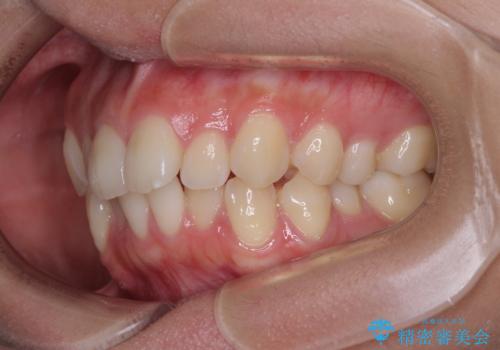

- デコボコを気にして来院された患者様です。

インビザラインでもワイヤー装置でも対応可能でしたが、自己管理の煩わしさの観点から、楽して治療のできるワイヤー装置を選択されました。

抜歯するほどではないものの、やや口元の突出感が気になっていたので、補助装置により上顎臼歯を後方に移動させることで、突出感改善を図ることとしました。